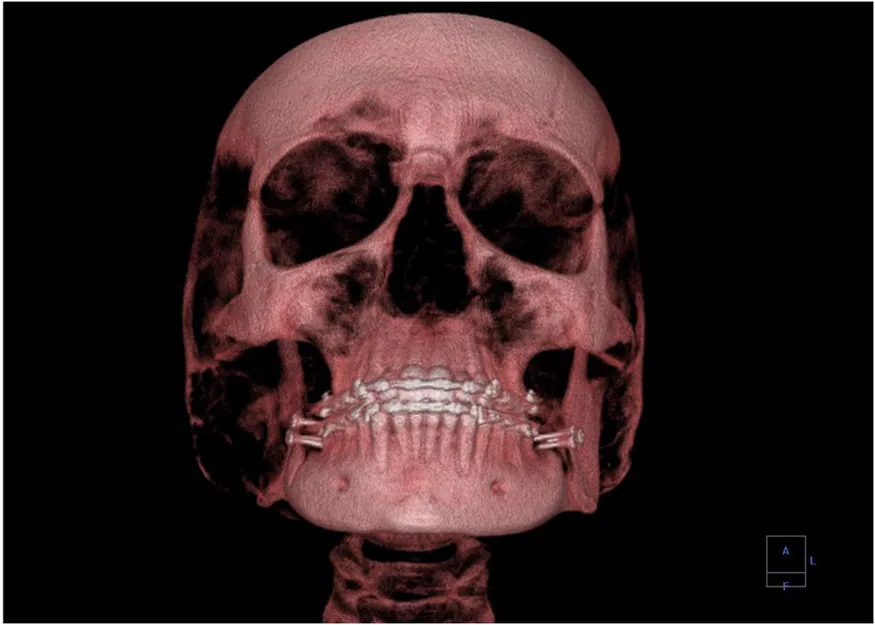

A standard x ray gives only a two-dimensional view of the object. Dense bones might hide images of soft tissue or organs. If you took another x ray from the side of the person (the first one being from the front), you would gain additional information. While shadow images are sufficient in many applications, far more sophisticated images can be produced with modern technology. Figure 30.25 shows the use of a computed tomography (CT) scanner, also called computed axial tomography (CAT) scanner. X rays are passed through a narrow section (called a slice) of the patient’s body (or body part) over a range of directions. An array of many detectors on the other side of the patient registers the x rays. The system is then rotated around the patient and another image is taken, and so on. The x-ray tube and detector array are mechanically attached and so rotate together. Complex computer image processing of the relative absorption of the x rays along different directions produces a highly-detailed image. Different slices are taken as the patient moves through the scanner on a table. Multiple images of different slices can also be computer analyzed to produce three-dimensional information, sometimes enhancing specific types of tissue, as shown in Figure 30.26. G. Hounsfield (UK) and A. Cormack (US) won the Nobel Prize in Medicine in 1979 for their development of computed tomography.

A 3-D image showing a human skull from the front.

Figure 30.26 This three-dimensional image of a skull was produced by computed tomography, involving analysis of several x-ray slices of the head. (credit: Emailshankar, Wikimedia Commons)